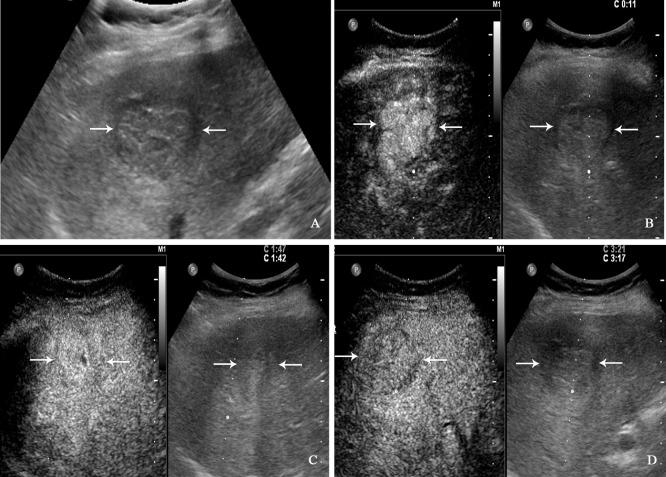

PHNET was more common in women (57.1%, 8/14 cases), and NBNC-HCC was more common in men (75.0%, 21/28) (=0.040). No significant differences were observed in etiology, tumor marker, and liver function between the two group (>0.05). Conventional ultrasound revealed that the tumor size of PHNET (10.1 ± 4.7 cm) was larger than that of NBNC-HCC (5.9 ± 3.8 cm) (=0.006). NBNC-HCC was predominantly hypoechoic, while the echogenicity of PHNET varied (=0.001). On CEUS, 57.1% (8/14) of PHNETs showed heterogeneous hyperenhancement, whereas 77.0% (21/28) of NBNC-HCC presented homogeneous hyperenhancement (=0.015). Furthermore, 35.7% (5/14) of PHNETs showed early washout (onset of washout <60 s), which was significantly different from that of NBNC-HCC (3.7%, 1/28) (=0.005).

CEUS is helpful in discriminating between PHNET and NBNC-HCC. PHNETs mainly present as a single mass with a large size (>10 cm) in the liver. The CEUS showed that most PHNETs exhibited heterogeneous enhancement in the arterial phase, washout in the portal venous and late phases and early washout being more likely than NBNC-HCC. However, more imaging features need to be evaluated in a larger sample.

PHNET在女性中更常见(57.1%,8/14例),而NBNC-HCC在男性中更常见(75.0%,21/28)(P=0.040)。两组在病因、肿瘤标志物及肝功能方面无显著差异(P>0.05)。常规超声显示,PHNET的肿瘤大小(10.1±4.7 cm)大于NBNC-HCC(5.9±3.8 cm)(P=0.006)。NBNC-HCC主要为低回声,而PHNET的回声各异(P=0.001)。在CEUS上,57.1%(8/14)的PHNET表现为不均匀高增强,而77.0%(21/28)的NBNC-HCC表现为均匀高增强(P=0.015)。此外,35.7%(5/14)的PHNET表现为早期廓清(廓清开始时间<60秒),这与NBNC-HCC(3.7%,1/28)有显著差异(P=0.005)。

CEUS有助于鉴别PHNET与NBNC-HCC。PHNET主要表现为肝脏内单个较大(>10 cm)肿块。CEUS显示,大多数PHNET在动脉期表现为不均匀增强,在门静脉期和延迟期廓清,且比NBNC-HCC更易出现早期廓清。然而,需要在更大样本中评估更多的影像学特征。